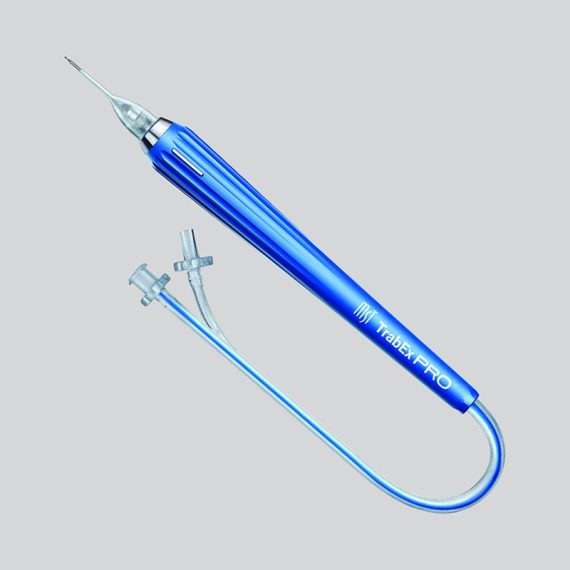

MST TrabEx PRO™MicroSurgical Technology's TrabEx Pro™ is an innovative dual-blade excisional...Code: 600050Explore

MST TrabEx PRO™MicroSurgical Technology's TrabEx Pro™ is an innovative dual-blade excisional...Code: 600050Explore -